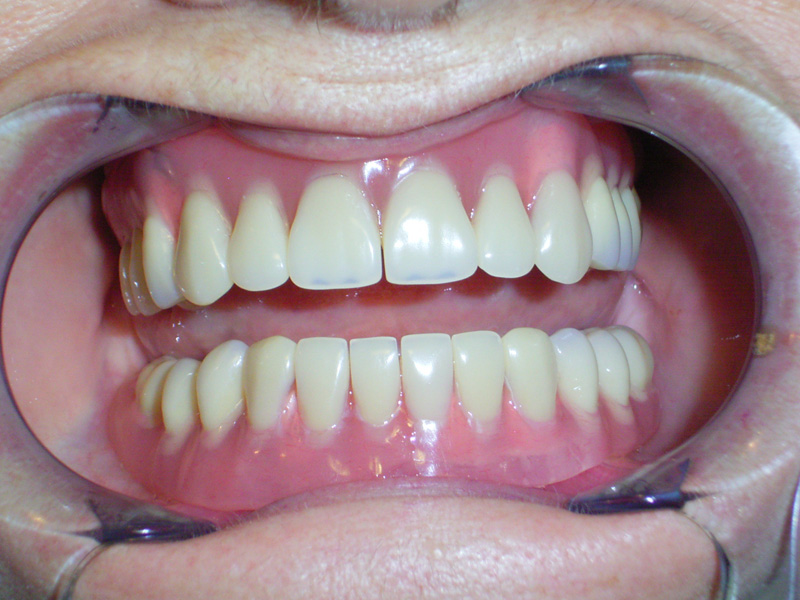

Implante - Galerie Foto

Caz I